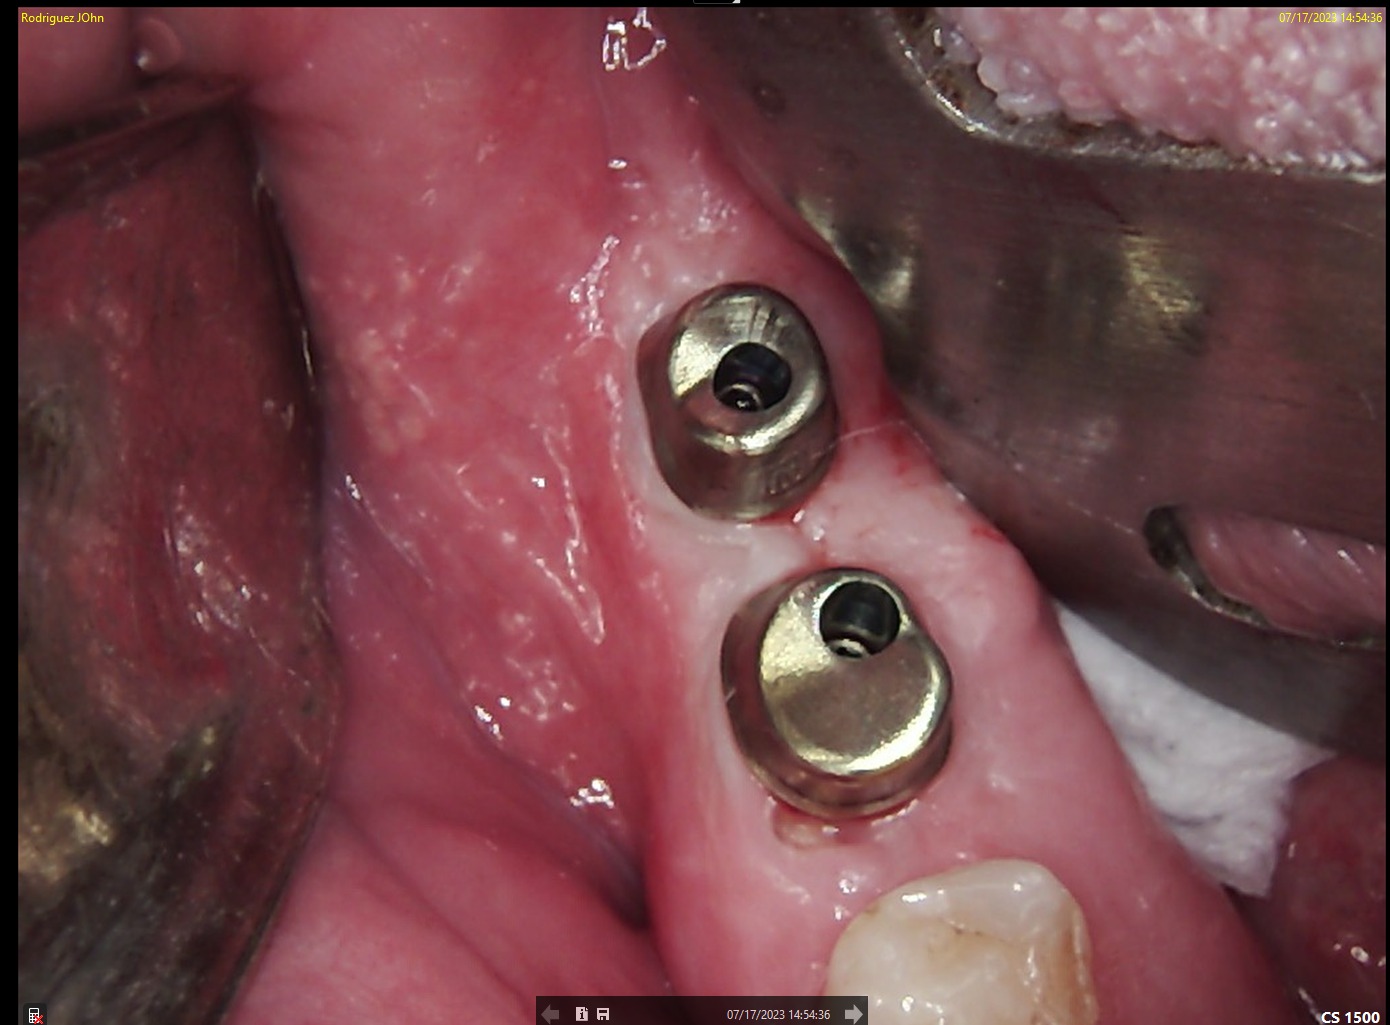

SURGERY

A flap approach was performed under local anesthesia. Osteotomies were prepared following the digital treatment plan, respecting biological principles and anatomical limitations. Two DSI Premium Mountless Implants were placed with high primary stability. The implants were positioned to allow optimal emergence profile and long term crestal bone preservation. Primary closure was achieved, and DSI Concave Healing Caps were placed to support soft tissue architecture during healing.

.jpeg)

HEALING STAGE